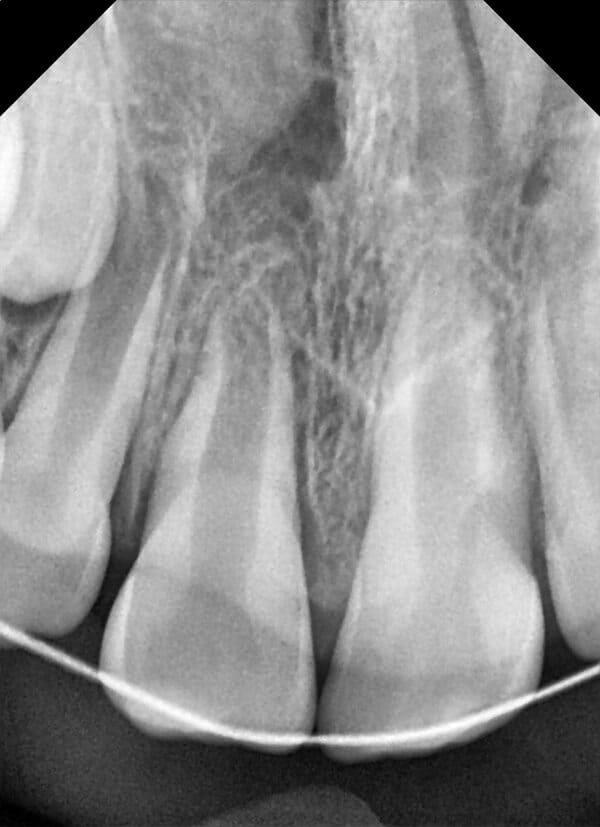

Травма постійних зубів. Олег Ковнацький.

Дівчинка 7 років, перше вересня, гойдалка… Вивих постійного зуба: якщо в такій ситуації зволікати, дитина може втрати постійний зуб назавжди. Батькам порекомендували нас і пацієнти одразу приїхали. Через складність і травматичність процедур вирішено проводити лікування в анестезіологічному супроводі. Зуб поставлений на місце (репонований), проведена хірургічна обробка і ушивання рани губи. Останнє фото через рік після травми: зуб на місці і корінь продовжує розвиватись, губа повністю загоїлась